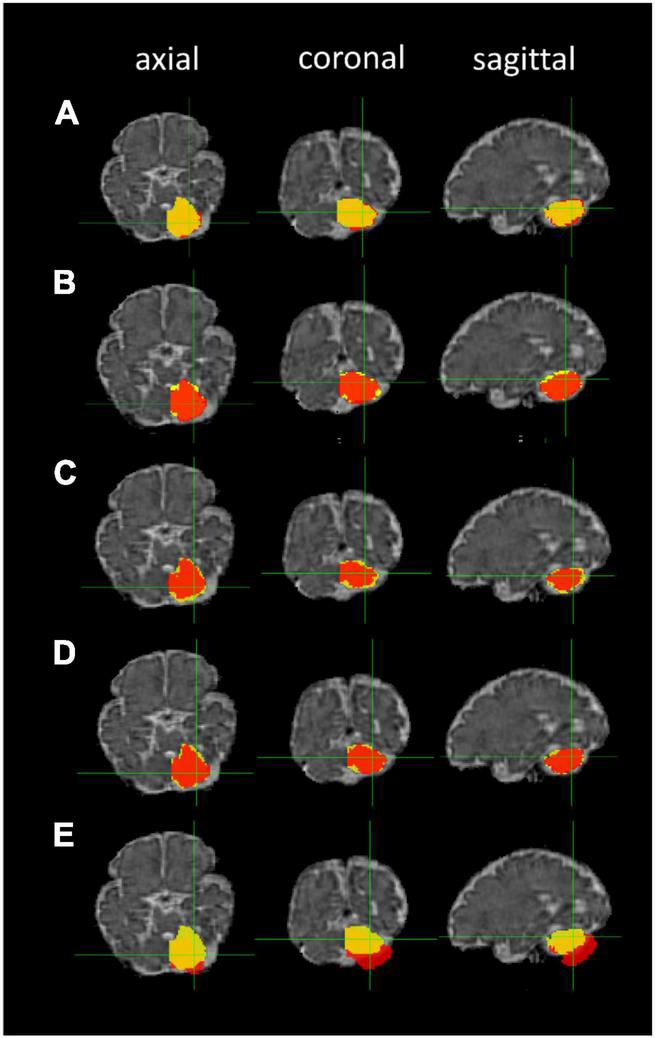

The ANTs- (5–10 h/dataset) and FLIRT-based (10 min/dataset) registrations of the 36-week GA fetal brain atlas into the native spaces of the individual fetal MR images were successfully processed in all participants. The median DSCs comparing the five image registration methods to the manual segmentation method were: (1) FLIRT linear registration (affine) using the correlation ratio similarity metric, (2) ANTs linear registration (rigid and affine) using the MI similarity metric (ANTs Lin MI), (3) ANTs linear registration using the CC similarity metric (ANTs Lin CC), (4) ANTs nonlinear registration (rigid, affine, and SyN) using the MI similarity metric (ANTs NL MI), and (5) ANTs nonlinear registration using the CC similarity metric (ANTs NL CC) for left and right cerebellum and thalamus segmentations. The cerebellar masks produced by the five registration methods using different similarity metrics are shown in Figure 6.

FIGURE 6

Cerebellar masks: registration-based segmentation (red) versus manual segmentation (yellow). The masks are shown in axial, coronal, and sagittal planes from left to right. Row (A) ANTs linear registration (MI); (B) ANTs linear registration (CC); (C) ANTs nonlinear registration (CC); (D) ANTs nonlinear registration (MI); and (E) FLIRT linear registration.

The median DSCs of the five registration methods for the cerebellum segmentations, thalamus segmentations, and both segmentations are listed in Table 4. Overall, the FLIRT linear registration resulted in non-optimal estimation with gross misalignment of the masks on the fetal MR image. The ANTs nonlinear registration (CC) had the highest median Dice similarity index. The ANTs non linear registration (MI) also demonstrated a very good performance.